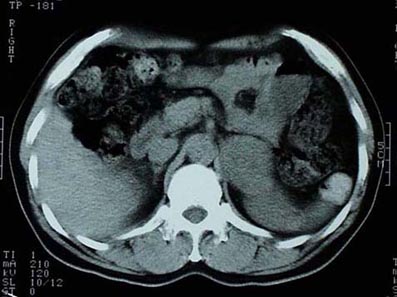

CaseYW01

- Age/Sex: 50M

- Chief Complaint: 頭痛,発汗過多,動悸,体重減少

- Clinical

Course: アルコール性肝炎にて経過観察中。最近1年間、高血圧症の診断で降圧薬を内服している。

- Lab. Data: 末梢血中濃度 Epinephrine 43 pg/ml (基準値 0-80),

Norepinephrine 31400 pg/ml (基準値 90-420), Dopamine 122 pg/ml

(基準値 0-30)

- Images:

- X-CT

- 131I MIBG,

48h

123I

MIBG, 24h

123I

MIBG, 24h

あなたの診断は What

is your first impression?